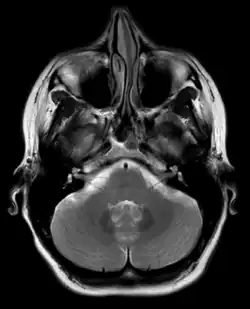

Die Diagnose einer Septumdeviation wird mittels äußerer Inspektion der Nase, vorderer Rhinoskopie, Endoskopie oder Computertomografie (CT) gestellt. Wie stark eine Septumdeviation die Nasenatmung behindert, kann mithilfe einer Rhinomanometrie gemessen werden. Außerdem sollte eine Riechprüfung durchgeführt werden.